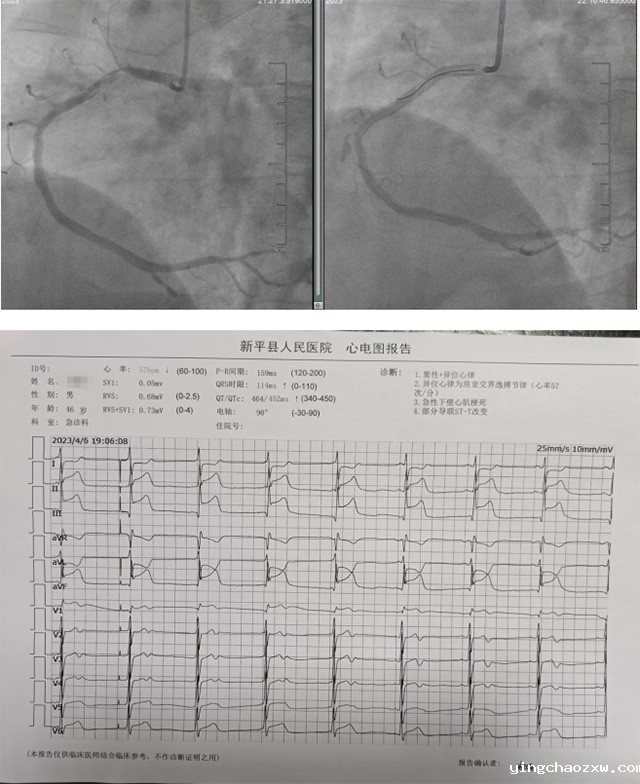

据悉,患者为男性,现年46岁,因“胸痛4小时”,于4月6日19:04到新利官网登录戛洒院区就诊。患者到达戛洒院区时表现胸痛剧烈,呼吸困难,心率缓慢,大汗淋漓,血压低于正常,值班医师立即为患者实施心电图检查,经总医院心电中心远程快速诊断为急性下壁心肌梗死。患者病情万分危急,若不及时开通病变血管,将会危及生命安全。“时间就是生命,急救分秒必争。”戛洒院区立即给予患者多巴胺泵入维持血压,并快速启动溶栓治疗,同时与家属协商为患者开展冠状动脉介入治疗事宜。经患者家属同意后,患者被120护送至北院区心血管内科介入导管室。北院区心血管内科介入团队立即为患者实施急诊冠状动脉造影检查,提示右冠近段狭窄95%(溶栓再通)。为了在最短时间内挽救患者生命,北院区心血管内科介入团队秉持“你若生死相托,我必全力以赴!”的仁医精神,争分夺秒为患者实施急诊PCI手术治疗(经皮冠状动脉介入治疗)。在患者右冠病变部位成功植入1枚冠状动脉支架后,患者病情迅速好转,最终转危为安。患者及家属对本次高质量的抢救非常满意,并向所有参与本次抢救的医务人员致以最诚挚的谢意!